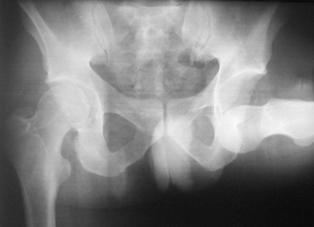

Fractura Malgaigne Fractura Malgaigne. Imagine CT

Fractura de

aripa iliaca stanga Fractura de aripa iliaca

stanga

Disjunctie sacro-iliaca stanga Disjunctie

sacro-iliaca stanga Aspect CT